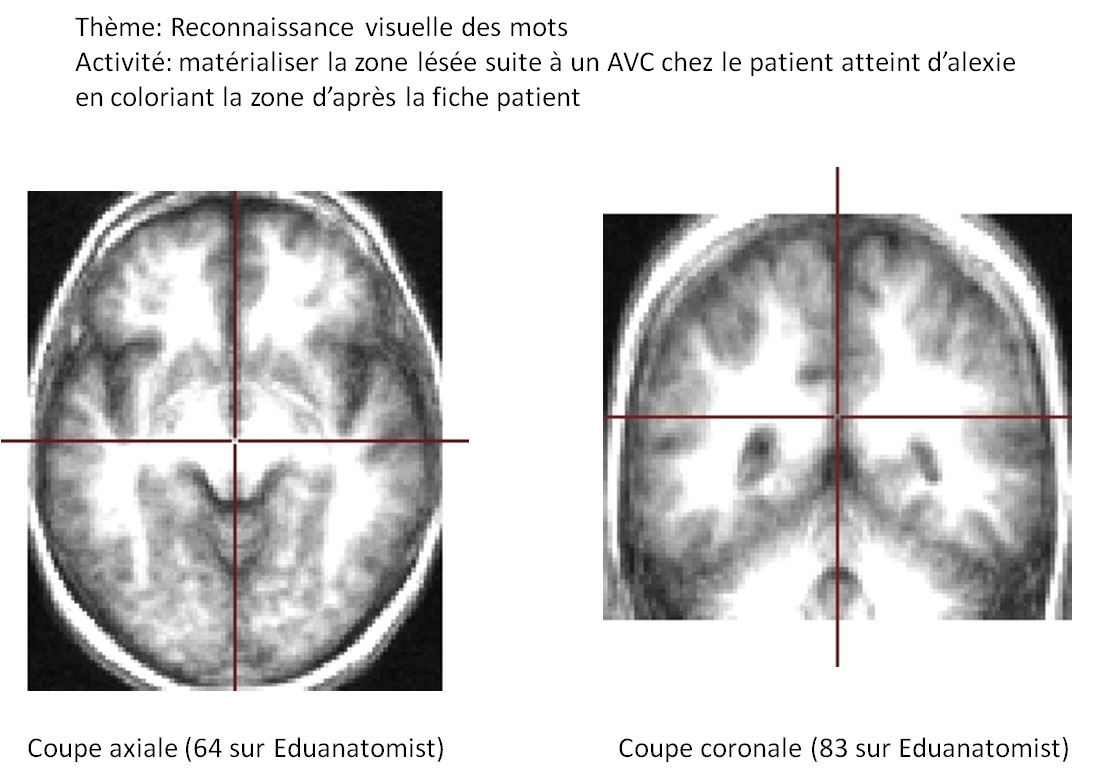

RECONNAISSANCE VISUELLE DES MOTS ET PLASTICITE CEREBRALE

activité1.png